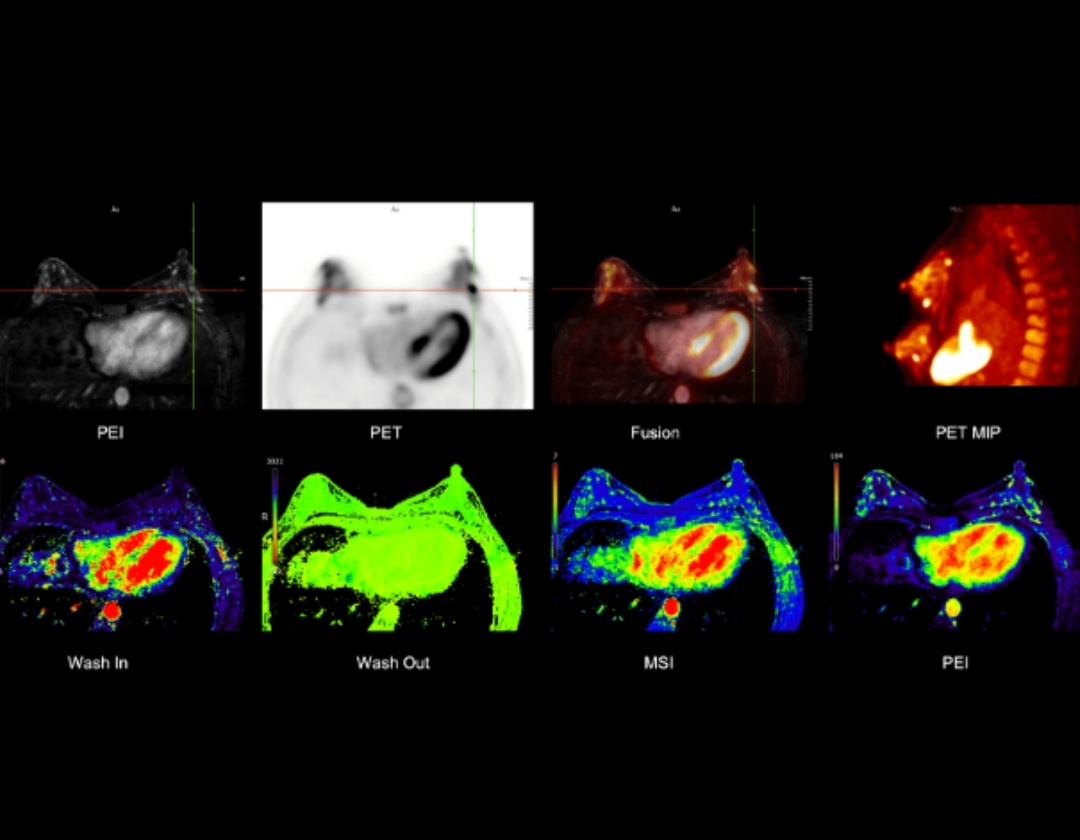

The uSync research platform facilitates new research opportunities, including simultaneous tracking of PET and MR tracers, simultaneous cardiac PET and MR, functional neurological PET/MR, and multi-parametric radiomics.

Multi-parametric PET/MR for Comprehensive Breast Evaluation